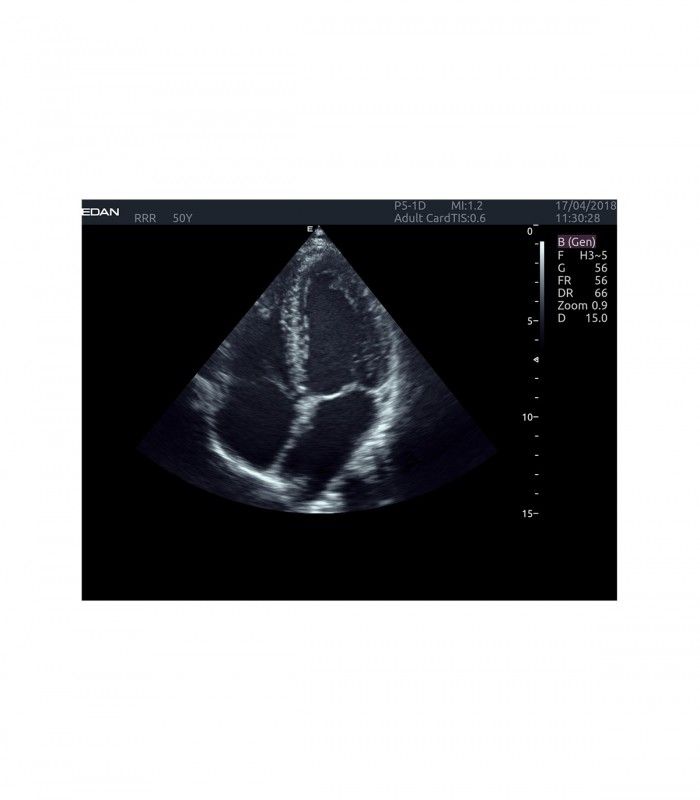

L’AX4 affiche une image claire et précise dans les différents modes grâce à de multiple technologies de traitement de l’image.

L’Imagerie Tissulaire Adaptative (TAI) ajuste automatiquement en temps réel de nombreux paramètres, dès la pose de la sonde sur le patient, afin d’afficher la meilleure qualité d’image, permettant ainsi au praticien de poser un diagnostic plus rapidement.

- Imagerie entièrement automatisée (modes B, couleur, doppler, M)

- THI : imagerie tissulaire harmonique